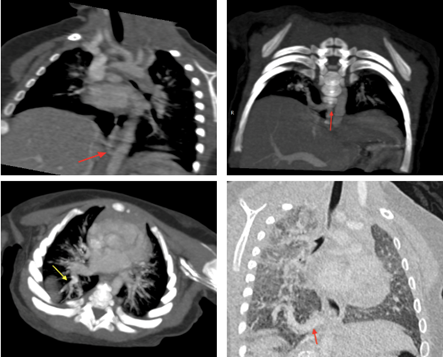

The diagnosis of this congenital anomaly is typically established through CT (Figure) or MR angiography, which defines the anatomy, detects the anomalous systemic arterial supply, reveals the venous drainage and rule out other potential thoracic pathologies [2,5].

Figure: CT scan illustrating a systemic artery (red arrow) originating from the abdominal aorta at the level of the diaphragm, prior to the emergence of the celiac trunk. Venous drainage is directed toward a dilated right inferior pulmonary vein (yellow arrow). These findings are consistent with a Pryce type I pulmonary sequestration.